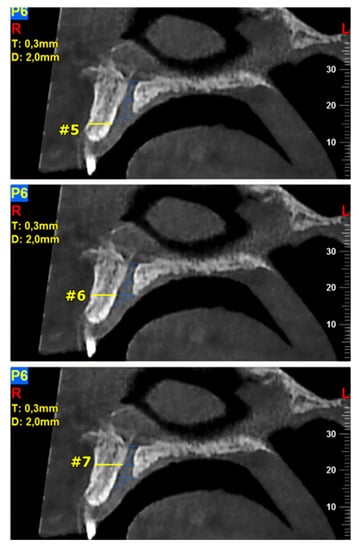

Figure 2.

The following landmarks were selected for the buccal osseous plate (BOP) analysis of the sagittal cone beam computed tomography (CBCT) images (all measurements in mm): #5—the crestal distance from the buccal border of the incisive foramen (IF) to the facial aspect of the BOP, #6—the distance midway from the buccal bone wall of the NPC to the facial aspect of the bone wall, using a horizontal line from the palatal border of the IF, #7—the most cranial distance from the buccal border in the middle of the NPC to the facial aspect of the buccal bone wall.